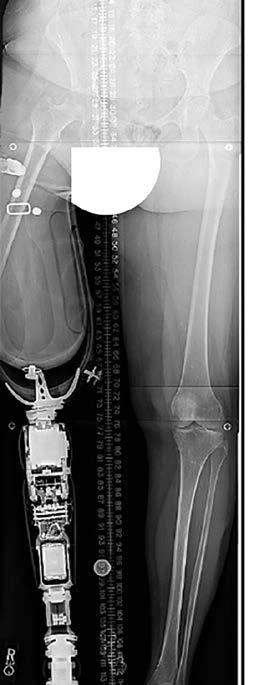

19 Osseointegracja – alternatywą dla klasycznego protezowania

Osseointegration – an alternative to classic prosthesis

Łukasz Kawik, Lidia Czwakiel, Wojciech Piwek, Paweł Cholewa

Na uwagę zasługuje praca o osseointegracji, która znakomicie koresponduje z artykułem redakcyjnym. Termin ten określa połączenie żywej kości z implantem, co niesie lepszy i długotrwały efekt wykonanej amputacji. Co więcej, osoby po amputacji zgłaszają dużą poprawę funkcjonalności, komfortu, równowagi, propriocepcji, a nawet emocjonalnego połączenia z kończyną. Cieszy fakt, że te nowoczesne zabiegi wykonywane są już w naszym kraju.

Another paper on osseointegration corresponds excellently with the editorial. This term describes the fusion of living bone with an implant, which carries a better and longer-lasting effect of the performed amputation. Moreover, amputees report significant improvements in function, comfort, balance, proprioception, and even emotional connection to the limb. Seeing that these state-of-the-art procedures are already being performed in our country is gratifying.